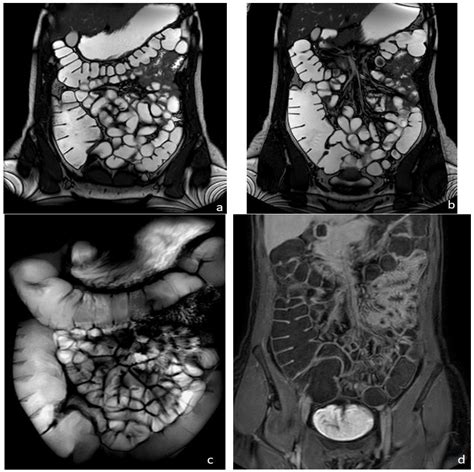

When your physician suspects an issue within your internal organs, they may recommend an MRI of abdomen to gain a clear, detailed picture of what is happening inside. Magnetic Resonance Imaging (MRI) is a sophisticated, non-invasive diagnostic tool that utilizes powerful magnets and radio waves to generate cross-sectional images of the structures in your abdominal area. Unlike X-rays or CT scans, an MRI does not use ionizing radiation, making it a preferred choice for many patients requiring detailed soft-tissue assessment of organs like the liver, gallbladder, pancreas, spleen, and kidneys.

An MRI of abdomen is rarely the first test ordered; instead, it is typically used to clarify findings from an ultrasound or CT scan or to provide a more detailed look at specific conditions. Doctors rely on this technology because it offers superior contrast resolution, allowing them to differentiate between healthy and diseased tissue with remarkable precision.

• Evaluating abnormalities in the liver, such as tumors or cirrhosis.

• Evaluating inflammation in the digestive tract.